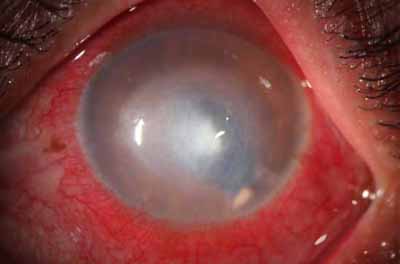

En su evolución se observará aumento del edema, aparición de un anillo inmunológico (Wessely), agrandamiento y coalescencia de los infiltrados que progresan hacia la formación de un absceso, queratolisis superficial, adelgazamiento y perforación corneal.

Anillo inmunológico de Wessely

- Es la expresión de la interacción de los antígenos extraños con los anticuerpos que se difunden desde los vasos limbares hacia el estroma.

- Representa la formación de un complejo inmune que activa el sistema del complemento.

- El anillo de Wessely contiene principalmente neutrófilos

- Puede aparecer en procesos no infecciosos

La vascularización y el hipopion son poco frecuentes en los estadios tempranos de la queratitis. Con el tiempo, en los estados avanzados de invasión estromal, aparecen vasos estromales